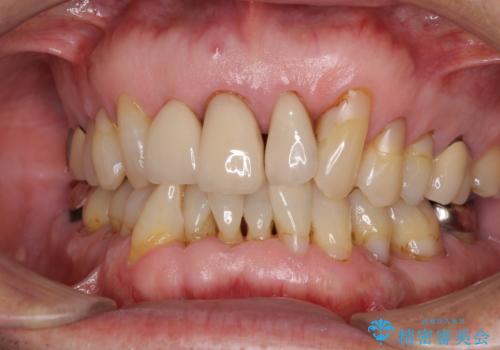

![[MTMを行い歯の神経を保存] 歯周補綴ブリッジの症例 治療前](https://seimitsushinbi.jp/wp/wp-content/uploads/2021/04/21310c2f37874ac2f2ba9939da2fee68-500x350.jpg?v=1618452125)